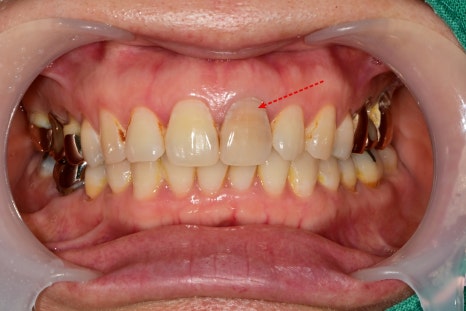

화살표로 표시된 부위는 치아 두께가 얇기 때문에

변색된 부분이 나중에 크라운에 비춰서 어둡게

보일 수 있는 부분이기 때문에 가능하다면

필요시 미백치료 후 보철을 해야 하는 경우도 있습니다.

치아 색 맞추는 단계

어둡게 비추는 부분을 커버하기 위해

여러 색을 대조해 보고 수정을 하는 과정이 필요했습니다.